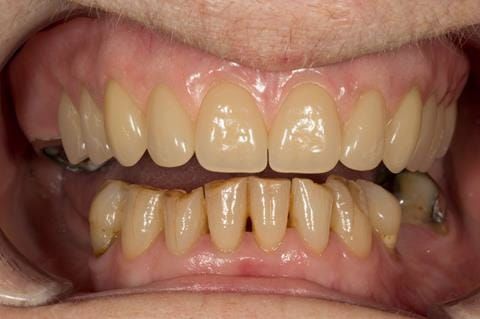

- Poorly fitting cobalt chromium based maxillary partial denture, which has been added to. This exhibited poor retention, stability and tissue fit (support). Unable to wear a new acrylic based denture.

- Eight mandibular anterior teeth worn incisal edges from now extracted maxillary anterior crowns. Gingivitis - owing to inadequate oral hygiene.

- Bruxism.

Following consultation and second discussion appointment the patient chose to have option 2 namely, a window denture - maxillary cobalt chromium based partial denture. The clinical situation and treatment process is shown in detail below with photographs. The patient was successfully rehabilitated with this and her quality of life considerably improved. The clinical work was provided by Finlay and the technical work by Rowan.